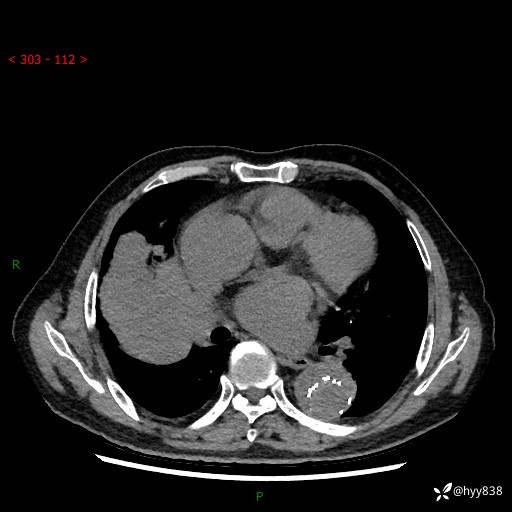

胸部CT平扫